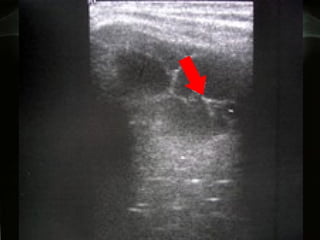

Toracentesis y análisis del líquido pleural. Requiere menos de 30 ml de líquido.  En derrames enquistados es útil la ecografía para localizar con precisión el líquido, y con ello hacer la toracentesis más fácil y sin riesgos

Toracentesis y análisisdel líquido pleural. Requiere menos de 30 ml de líquido. En derrames enquistados es útil la ecografía para localizar con precisión el líquido, y con ello hacer la toracentesis más fácil y sin riesgos